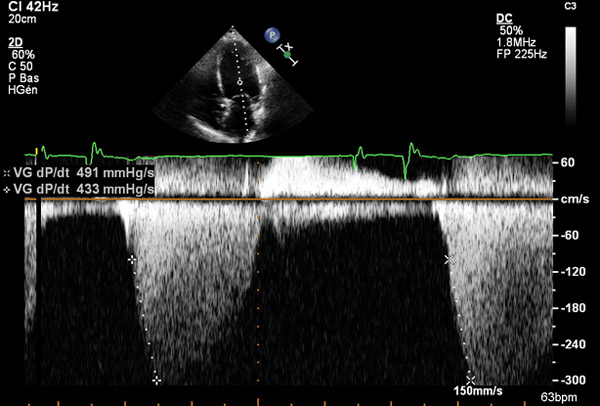

dP/dt : toujours d’actualité pour évaluer les pressions de remplissage VG ?

Vous avez dit dP/dt ?

Est-ce toujours d’actualité à l’époque du doppler tissulaire ?

Certainement oui, si on en juge par le nombre de publications qu’on retrouve sur PubMed en rentrant le mot clé « dP/dt ».

En cas d'insuffisance mitrale, ce rapport permet, en utilisant la loi de Bernouilli simplifiée, d’évaluer la contractilité et les pressions de remplissage du ventricule gauche.

Pour rappel, ce rapport se calcule à partir du flux d’IM. Il faut pour cela mesurer le temps entre les